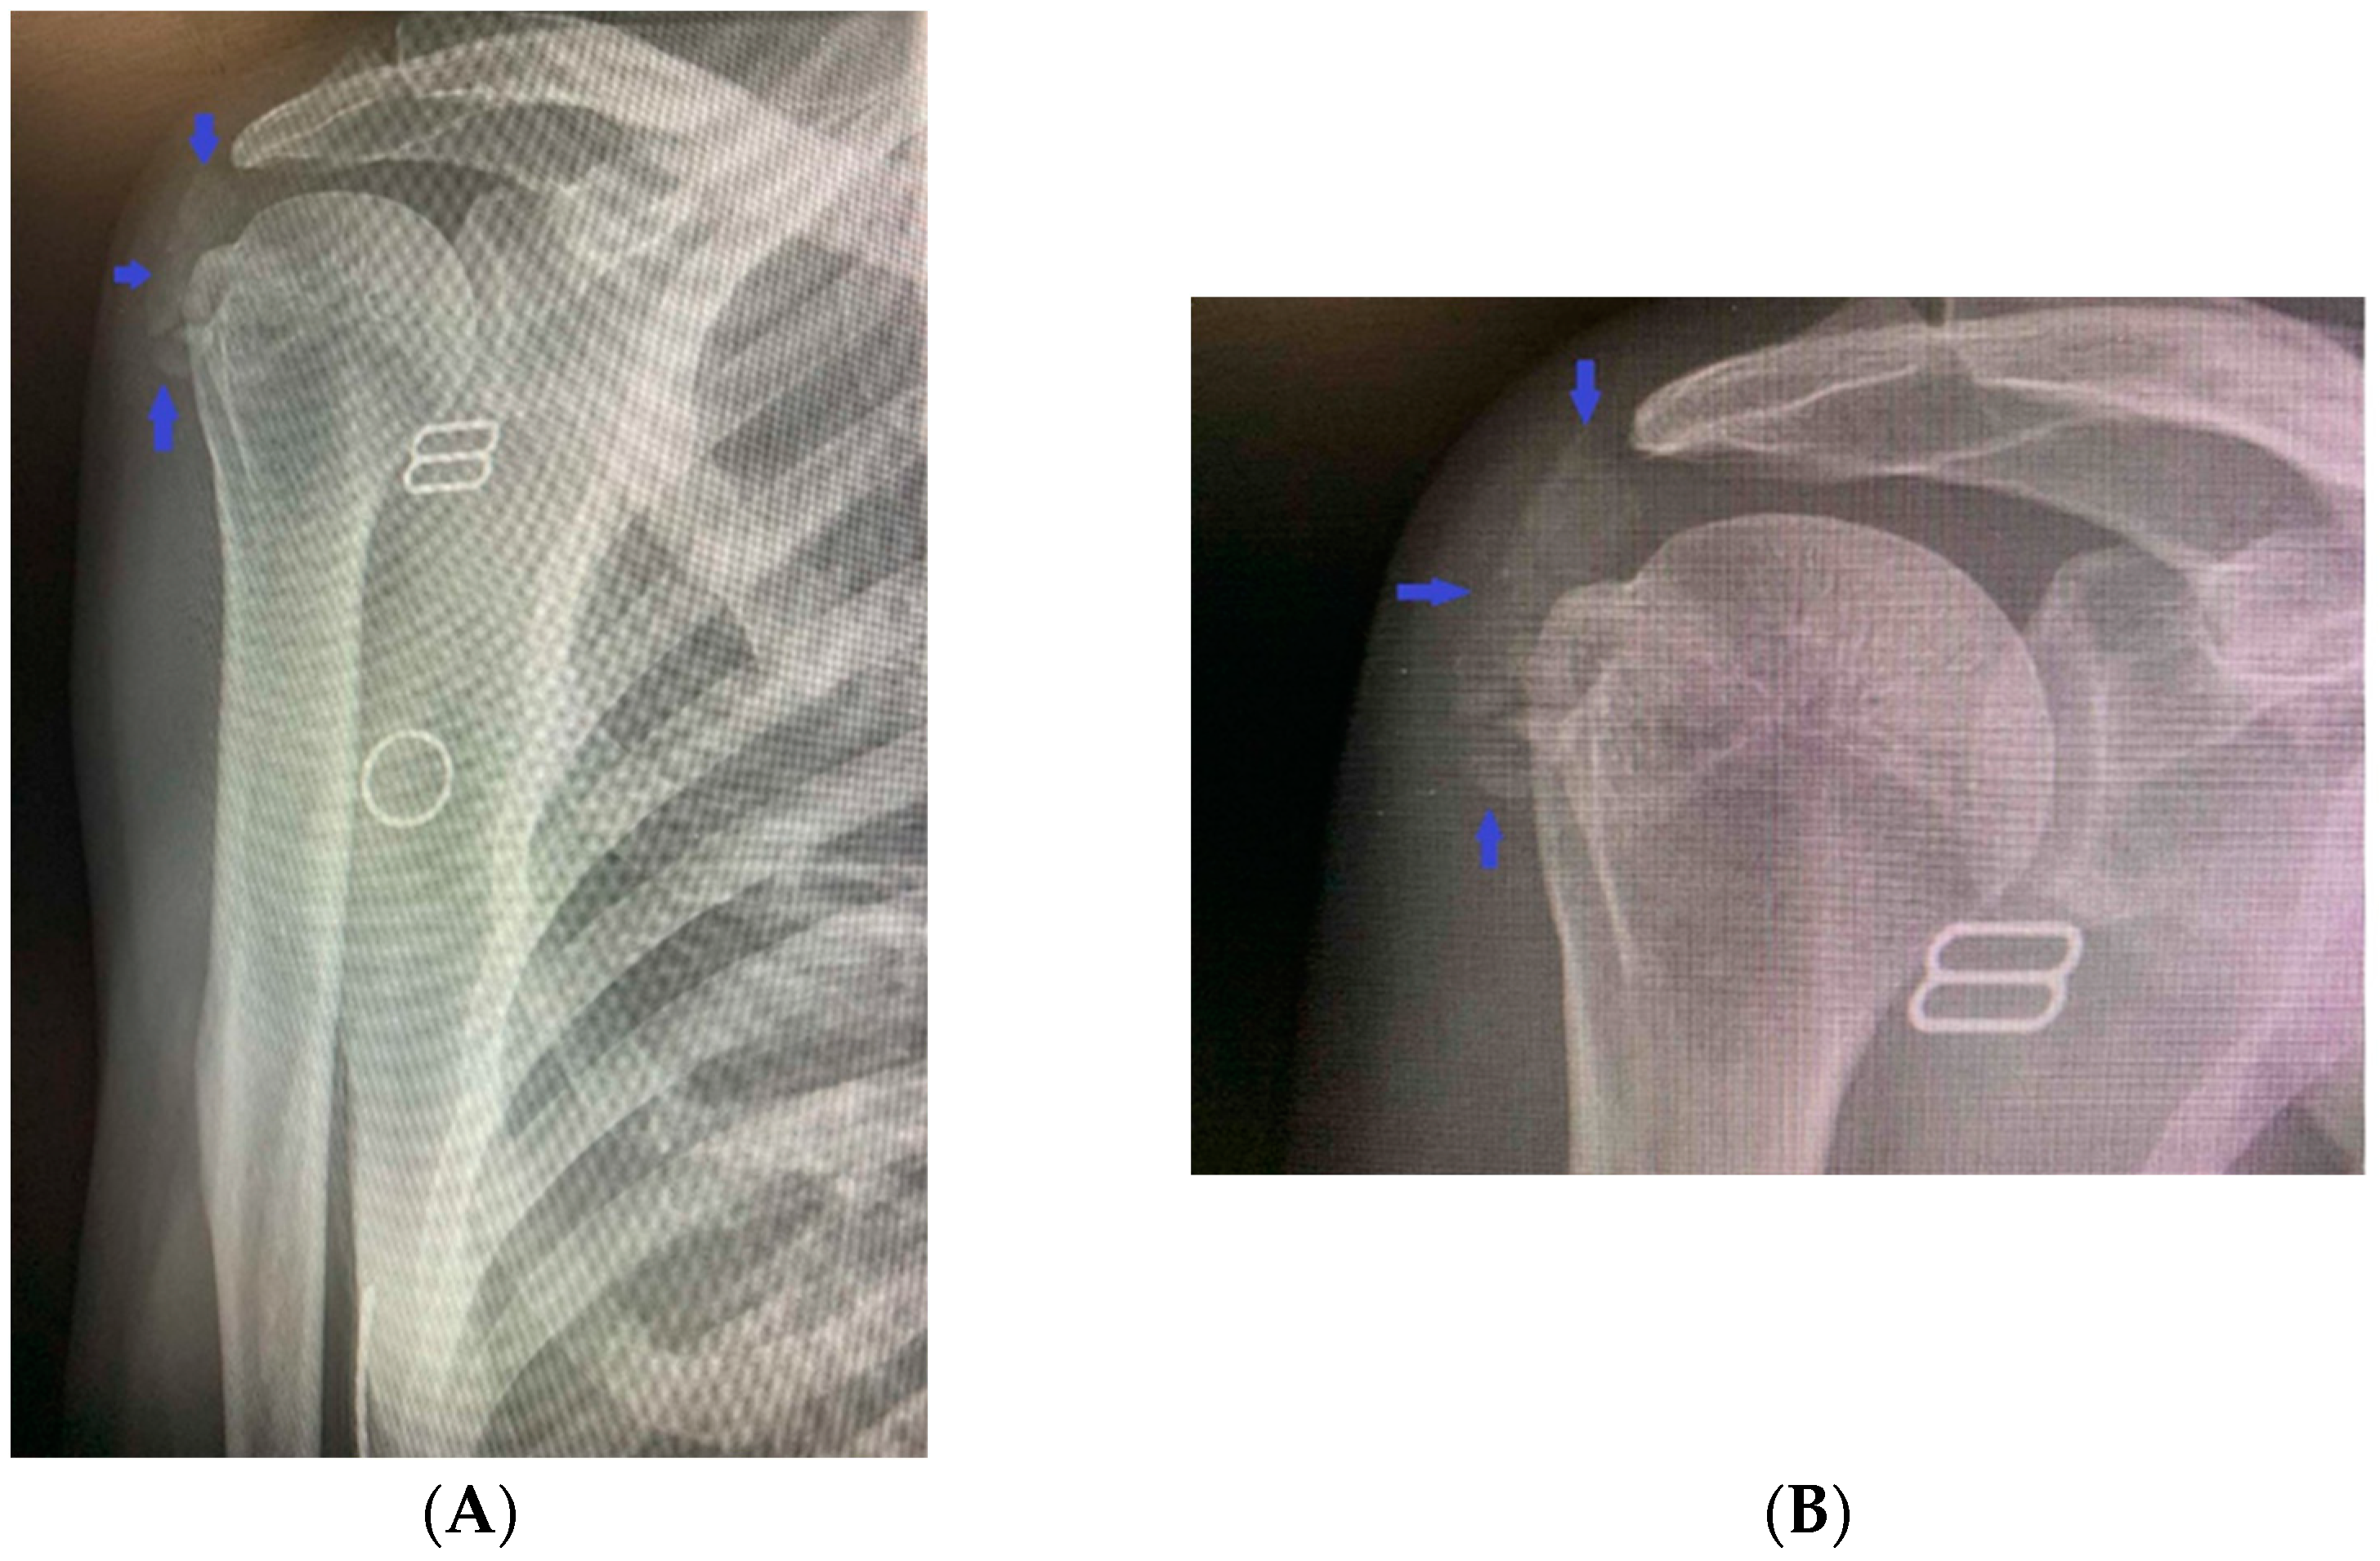

2. Clinical Case Presentation